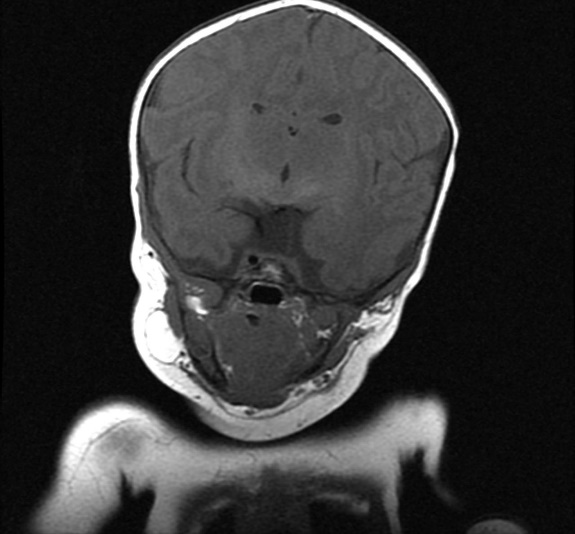

MRI findings showed the lack of the normal flow void of the left internal carotid canal and the first part of the left middle cerebral artery (Figures 1 and 2). The pituitary gland is flat. No evident anterior or posterior pituitary gland tissue or pituitary stalk is observed. The pituitary gland's strong posterior signal is not detected in situ or

ectopic. The left medial cerebral artery originates within the posterior circulation, and the left internal carotid artery cannot be seen. No intra, supra, retro or parasellar masses. Normal MRI appearance of the optic chiasm and corpus callosum. Otherwise, normal MR appearance of the brain parenchyma with no definite focal lesions. Diagnosis of congenital panhypopituitarism associated with agenesis of ICA was made.

a)

b)

c)

d)

Figure 1. a-c) figures showing MRI brain sagittal views of the patient where the pituitary sella is flat. No obvious anterior or posterior pituitary gland tissue or pituitary stalk is seen. The posterior pituitary bright signal is not visualized in site or ectopic. d) coronal MRI scan showing absence of pituitary gland tissue.

Generally, no intra, supra, retro, or parasellar masses. Normal MRI appearance of the optic chiasm and corpus callosum. Otherwise, normal MR appearance of the brain parenchyma with no definite focal lesions.